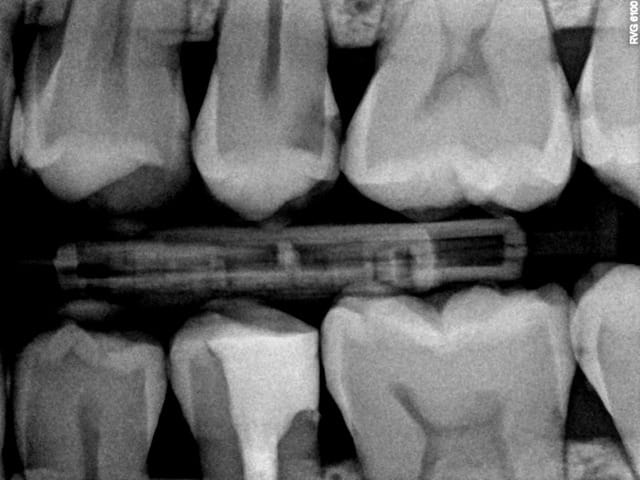

J'y travaille pour trouver un moyen simple et efficace pour poser la digue dans toutes les situations comme celle ci dessous. Tiens c'est tout frais, endo sc33 en 1 temps, 1H 15 et encore je n'ai pas d'assistante au fauteuil.

Pulpite indication endo. perte de substance: Indication onlay , mais pas dans le panier de soins donc sc 33, couronne coulée : patiente CMU.

Dis donc chicot t'es peut être le roi de l'endo mais au niveau économie tissulaire , ouverture de chambre , tu utilises un black et decker comme contre angle ?... t'y vas pas de main morte ... t'aurais peut être pu éviter le tenon alors , et qui sait la couronne .... et puis un genre screw post titane ? avec un matériau plastique perso je trouve pas ça terrible ... mais je ne suis qu'une petite dentiste qui utilise encore l'amalgame ... houuuu la méchante .....bon et puis la (ou le ) mitrailler comme ça pendant le soin juste pour nous montrer , faut pas tu sais , tu perds un temps fou ... après le temps de poster tout ça ..... t'imagines le temps perdu pour la rentabilité du cabinet ....